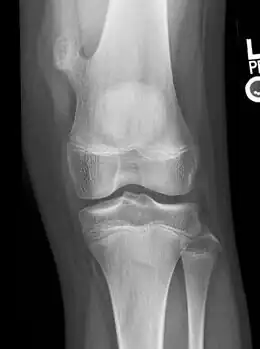

Osteochondroma arising from the thigh bone, near the knee